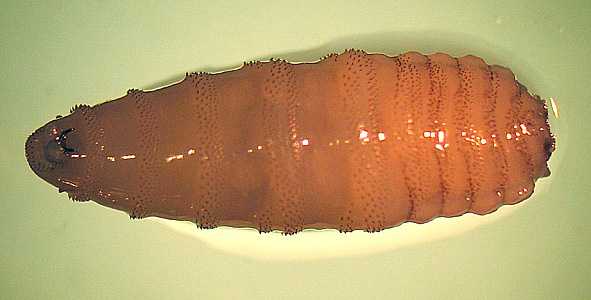

A 25-year-old man, who recently returned from a trip to Brazil, presented to his health care provider with a festering lesion on his forehead. The patient also complained of feeling things moving under his skin.